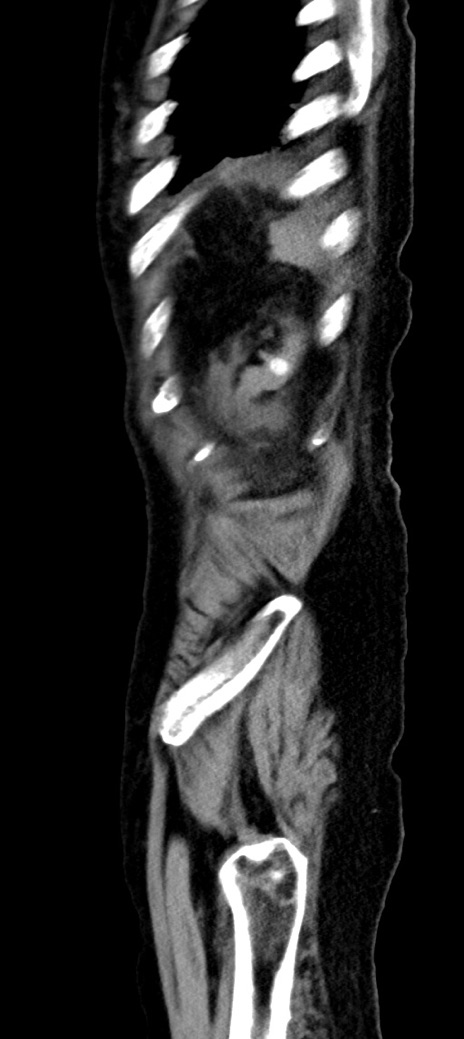

症例40(矢状断像)他院1日前

【症例】90歳代女性

【主訴】腹痛・嘔吐

【現病歴】 食欲低下、嘔吐があり昨日他院受診。肺炎と診断され入院となる。入院後より腹部全体に圧痛あり。胃管留置され経過みていたが、症状持続するため、

当院転院となる。

【既往歴】胸椎圧迫骨折、胆石症

【身体所見】腹部:中央に激痛あり、圧痛あり、反跳痛不明

【データ】WBC 17100、CRP 18.82